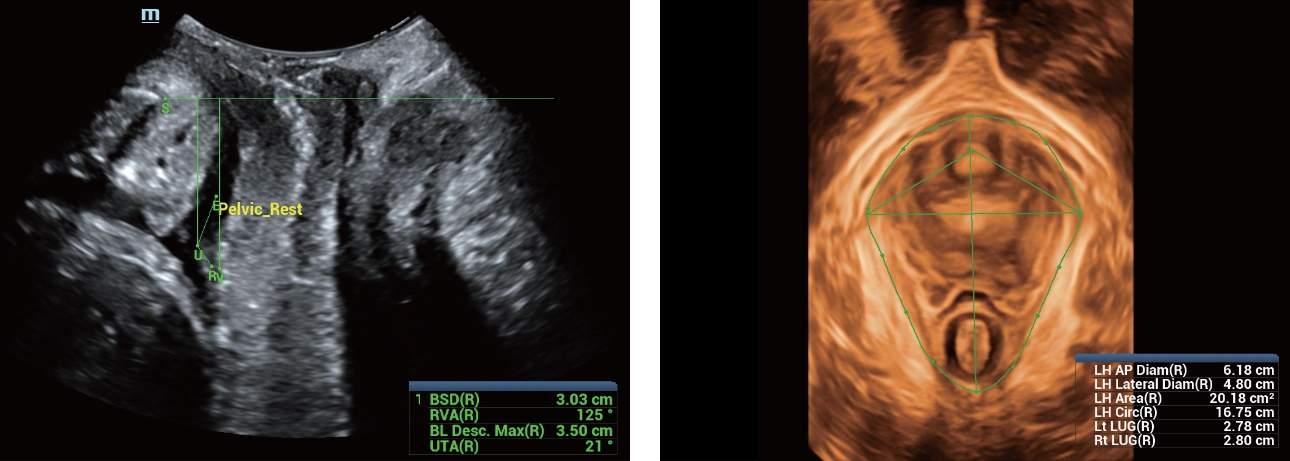

AdemÃĄs de una calidad superior de la imagen, el Resona 7 tambiÃĐn mejora las capacidades de investigaciÃģn clÃnica gracias al revolucionario V Flow para la evaluaciÃģn hemodinÃĄmica vascular y la adquisiciÃģn de planos mÃĄs inteligente a partir de un conjunto de datos 3D para el diagnÃģstico CNS fetal. Combinando el funcionamiento multitÃĄctil mÃĄs intuitivo basado en gestos y todas las funciones clÃnicas esenciales, el Resona 7 estÃĄ realmente encabezando nuevas ondas en la innovaciÃģn del campo del ultrasonido.